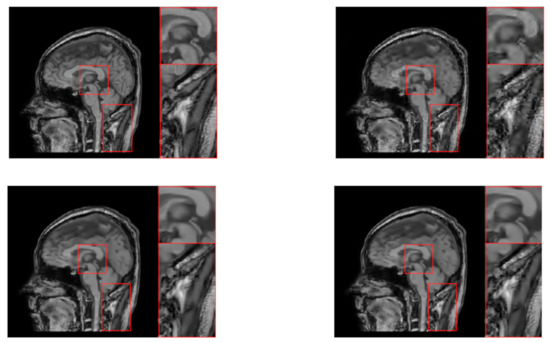

| “head2” | ||||||||||||

| SRD-DDTF | NLR-DDTF with | NLR-DDTF with | ||||||||||

| err | corr | psnr | time | err | corr | psnr | time | err | corr | psnr | time | |

| 15 | 29.38 | 92.34 | 22.47 | 495.41 | 29.21 | 92.39 | 22.52 | 888.51 | 29.22 | 92.39 | 22.52 | 1653.06 |

| 30 | 20.71 | 96.28 | 25.51 | 914.76 | 15.66 | 97.87 | 27.93 | 1284.95 | 15.44 | 97.93 | 28.05 | 1953.55 |

| 45 | 16.94 | 97.54 | 27.25 | 1378.70 | 10.04 | 99.13 | 31.80 | 1718.87 | 9.90 | 99.15 | 31.91 | 2443.62 |

| 60 | 15.37 | 97.98 | 28.09 | 1773.86 | 7.01 | 99.58 | 34.91 | 2290.07 | 6.939 | 99.58 | 35.00 | 2861.41 |